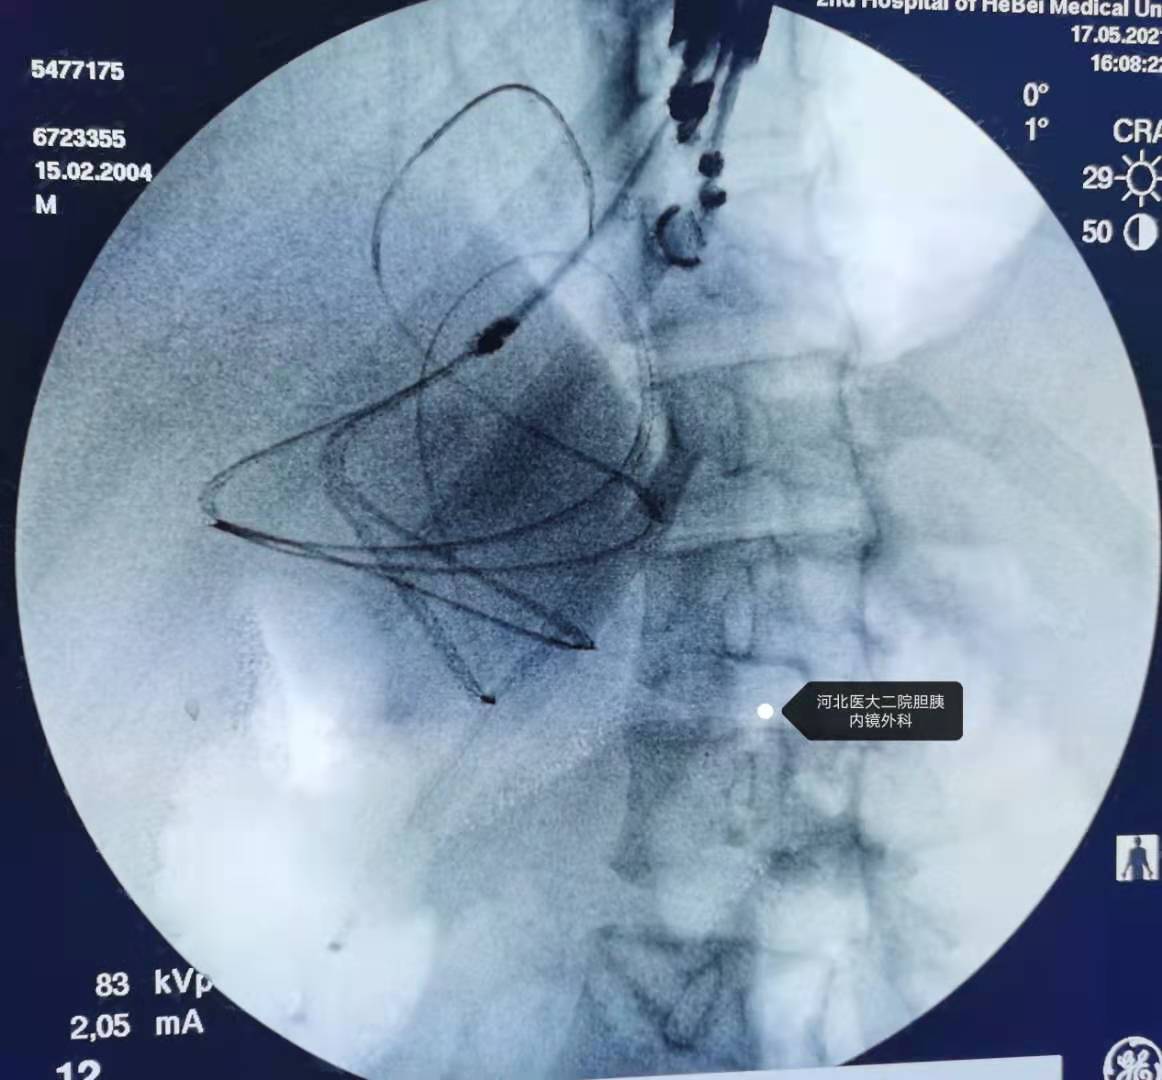

17岁男性,一个半月前骑“鬼火”出现事故,车把撞击腹部,当时无症状,近10天出现腹痛,近2天腹痛加重,遂试行ERCP。

因为是超滑导丝,不能将切开刀换Soehendra支架取出器,后来换了普通导丝,就再也进不去了,考虑时间比较长,所以直接下了胰管支架。